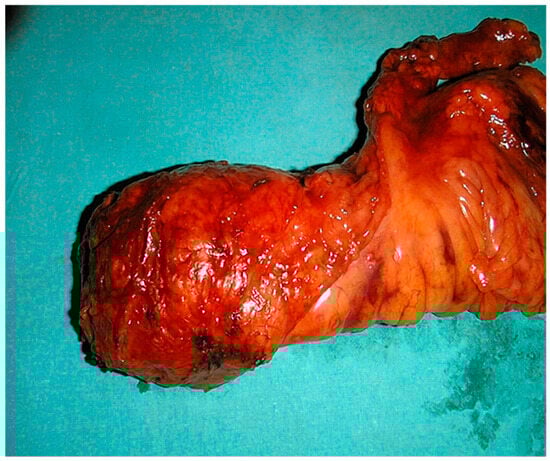

Colorectal cancer is among the most common forms of cancer, with approximately a third of all cases localized in the rectum [1]. It shows a male predominance with a male-to-female ratio of approximately 1.5:1, with a median age at diagnosis ranging from 60 to 65 years. Furthermore, the incidence of locally advanced rectal cancer (LARC) accounts for approximately 30–40% of all rectal cancer cases [2]. While early-stage tumors can be completely removed with surgery alone, the standard procedure for LARCs that are determined as a T3/T4 tumor or a tumor of any stage with positive lymph nodes, nowadays, includes the implementation of neoadjuvant chemoradiotherapy (nCRT) as a starting treatment followed by surgical resection (Figure 1) [2,3,4]. It is shown that this therapeutic approach lowers the risk of further cancer spreading and improves overall survival [5]. On histopathological enema, the pathological response to therapy classified by Mandard is the most commonly used scale. It ranges from tumor regression grade (TRG) 1, where it is only visible therapy—induced fibrosis, meaning complete response, to 5, meaning no response or progression [6].

Figure 1.

Surgical specimen of total mesorectal excision (TME).